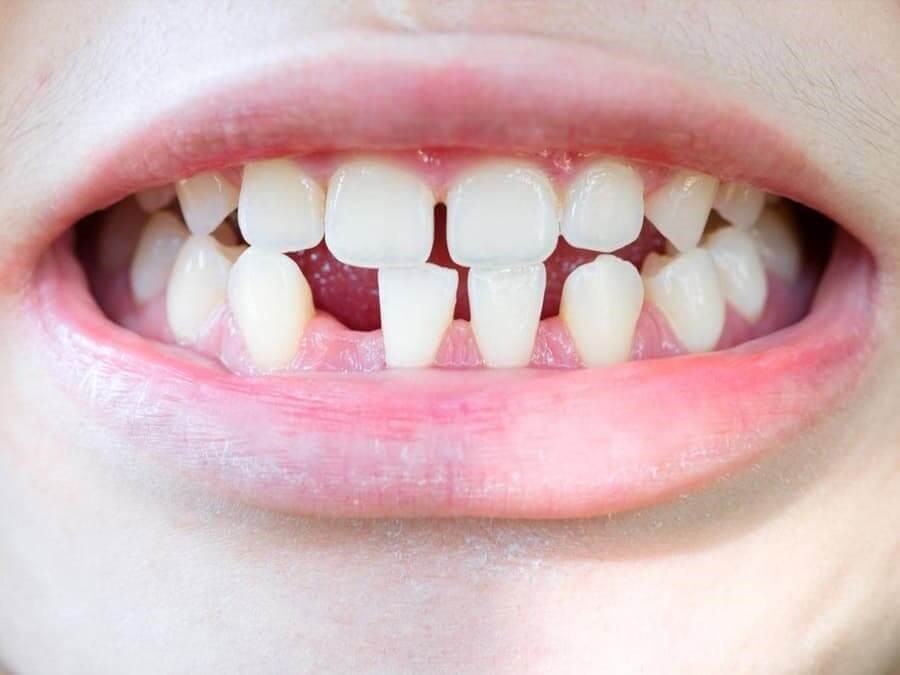

Khi đến tuổi mọc hoặc thay răng nhưng ba mẹ vẫn chưa thấy bé mọc răng là trường hợp phổ biến ở rất nhiều trẻ.

Nếu thiếu răng ở khu vực răng cửa, răng nanh sẽ gây ảnh hưởng trực tiếp đến tính thẩm mỹ. Điều này sẽ làm trẻ tự ti, e ngại khi giao tiếp.

Răng mọc thiếu có thể làm cho các răng còn lại trên cung hàm mọc lệch lạc hoặc nghiêng về vị trí đang trống nhiều hơn. Điều này có thể làm rối loạn khớp cắn, viêm nướu, tụt lợi thậm chí là gây đau khớp thái dương hàm.